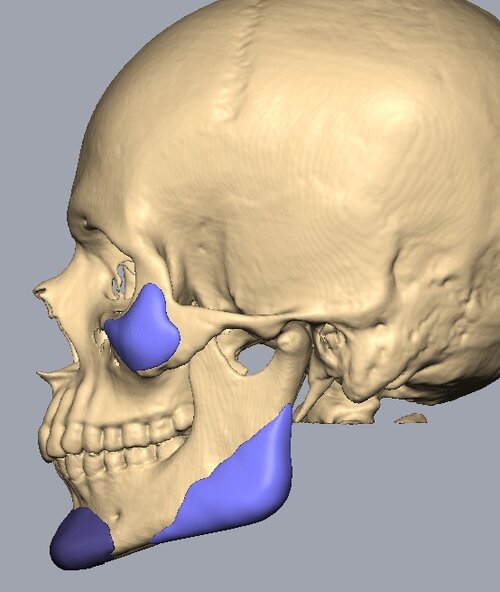

Recieved the draft 1 of the design, what changes should i ask for?? a couple of things i can think of are malar implants not giving enough lateral protrusion, gonion flaring.

I also am planning to include infra implants as well.